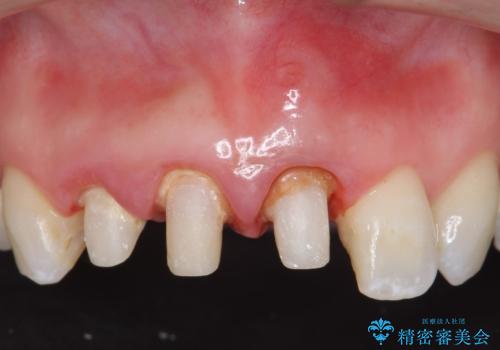

- 前歯の長さが違うのが気になるといらっしゃった方の症例です。

根尖病変を認めたため再根管治療を行った後、オールセラミッククラウン(スペシャル)にて補綴を行いました。

歯肉の腫れをより改善するため歯周外科を提案しましたが希望されませんでした。